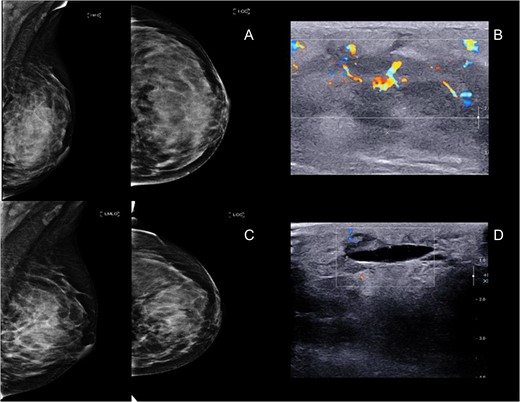

A 24-year-old female came with a history of asymmetrical enlargement of left breast for 4 months. The physical examination revealed asymmetrical enlargement of left breast with a large ill-defined lump mainly occupied in the upper inner quadrant. No skin discoloration or ulcer was seen (Fig. 1). Digital mammography with tomosynthesis (Hologic Selenia Dimensions, MA, USA) demonstrated extremely dense breasts with asymmetrical enlargement of the left breast. There was a large ill-defined mass mainly occupying at upper inner quadrant. No associated architectural distortion or suspicious microcalcifications were seen. Additional ultrasonography showed an ill-defined infiltrative mixed hypoechoic and hyperechoic mass at the same area. This mass demonstrated multiple vascular structures and a large arterial feeder. There were few benign left axillary lymph nodes (Fig. 2).

(A and B) Mammogram and ultrasound showed an ill-defined big mass at left mid inner quadrant with hypervascularity, subdermal edema and overlying skin thickening. (C and D) Mammogram and ultrasound post radiation showed 5.4 × 2.4 cm2. Ill-defined mass at left upper to mid inner quadrant with interval decreased internal hypervascularity.